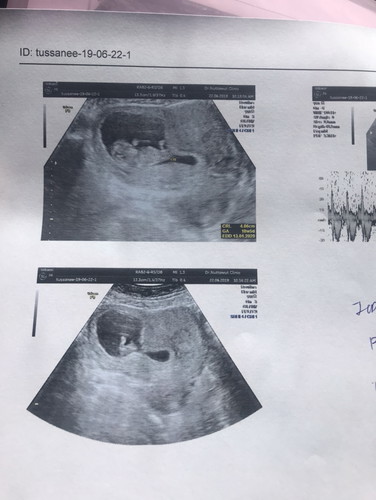

มดลูกรูปหัวใจ

อายุ 28 ปีค่ะ ท้องแรก ทราบว่าตังครรภ์ตอน5wks อัลตราซาวด์ครั้งแรกคุณหมอ บอกอาจมีมดลูกเป็นรูปหัวใจ รออัลตราซาวด์อีก1เดือนเพราะยังดูไม่ชัด ตอนนี้ 10wks หมอยืนยันว่าเป็นมดลูกรูปหัวใจ น้องเติบโตปกติ แต่จะมีภาวะเสี่ยง ต่อการแท้งและคลอดก่อนกำหนดสูง ไม่มีวิธีรักษา ต้องคลอดก่อนถึงจะผ่าตัดแก้ไขได้ ใครพอจะมีประสบการณ์บ้างไหมค่ะ